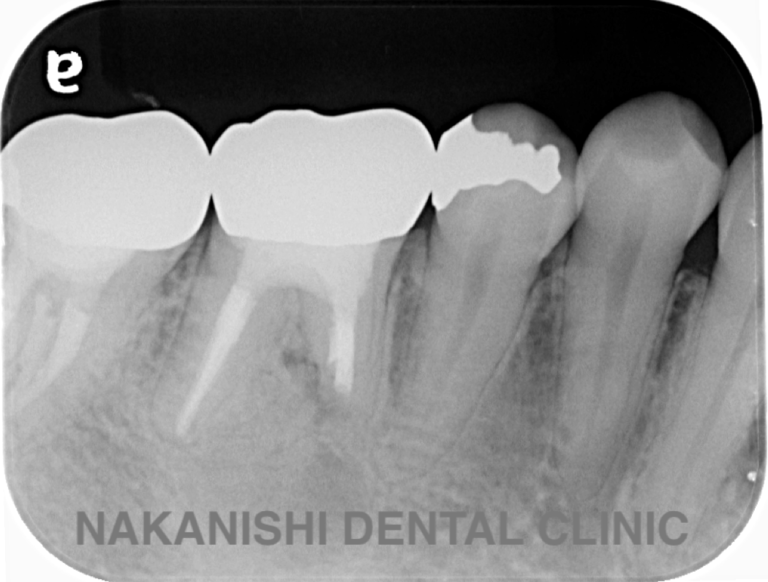

case 4.

治療前

治療後

| 主訴 | 右下奥歯が痛い。 他院で『膿の袋が大きいため抜歯』と言われセカンドオピニオン希望でご来院。 |

|---|---|

| 治療期間 | 約半年(6か月) |

| 治療費 | 約5万円 |

| 治療内容 | ラバーダム、マイクロスコープ下にて根管治療を実施し、歯根端切除を行う。歯茎の腫れは消失し違和感や痛みも消失した。 |

| 治療のリスク | マイクロスコープやCTを使用し、可能な限り精密な根管治療を行っていますが、歯根の形態や病変の大きさ、過去の治療履歴などにより、治癒が得られない場合があります。 また、治療後に再感染や歯根破折が生じることもあり、その場合は再治療や抜歯が必要となることがあります。 治療結果には個人差があり、すべての症例で同様の経過を保証するものではありません。 |